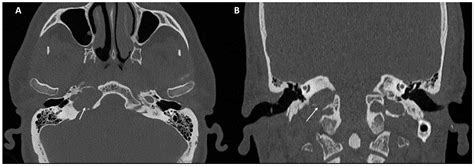

Typical and Atypical Symptoms of Petrous Apex Cholesterol Granuloma ...

mdpi.com